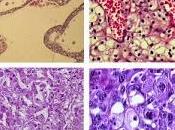

Axitinib avec ou sans ajustement approprié de la dose pour traitement de premièr...

Carcinome rénal à cellules claires. 1a: Fuhrman1 (HES x 40) , 1b: Fuhrman2 (HES x 100), 1c: Fuhrman3 (HES x 100), 1d: Fuhrman4 (HES x 200). Lire la suite

Le 21 octobre 2013 par Tartempion77